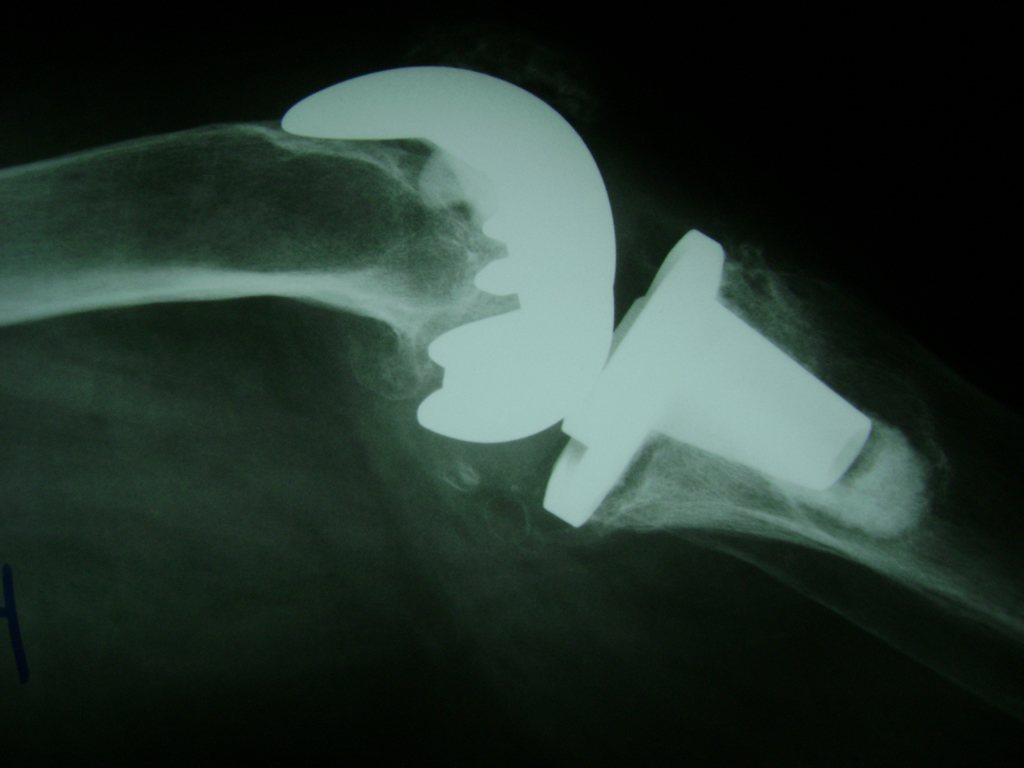

Cirugías de Rodillas